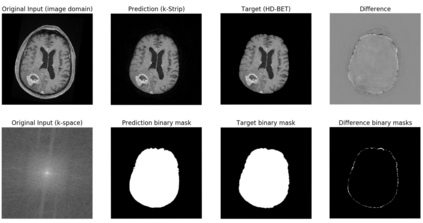

Objectives: Present a novel deep learning-based skull stripping algorithm for magnetic resonance imaging (MRI) that works directly in the information rich k-space. Materials and Methods: Using two datasets from different institutions with a total of 36,900 MRI slices, we trained a deep learning-based model to work directly with the complex raw k-space data. Skull stripping performed by HD-BET (Brain Extraction Tool) in the image domain were used as the ground truth. Results: Both datasets were very similar to the ground truth (DICE scores of 92\%-98\% and Hausdorff distances of under 5.5 mm). Results on slices above the eye-region reach DICE scores of up to 99\%, while the accuracy drops in regions around the eyes and below, with partially blurred output. The output of k-strip often smoothed edges at the demarcation to the skull. Binary masks are created with an appropriate threshold. Conclusion: With this proof-of-concept study, we were able to show the feasibility of working in the k-space frequency domain, preserving phase information, with consistent results. Future research should be dedicated to discovering additional ways the k-space can be used for innovative image analysis and further workflows.